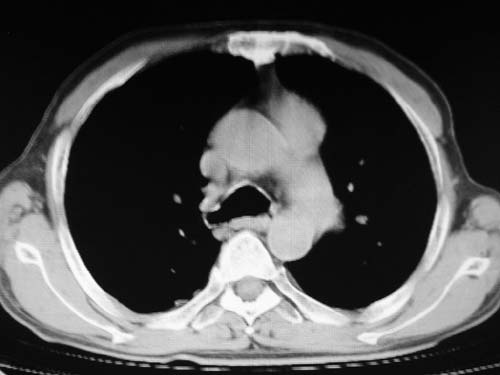

男,80岁

肺a高压征[左肺a狭窄?];肺,胸膜tb

右肺上叶结核;左肺门占位?建议增强扫描.

左下肺静脉扩张,原因?建议cta

看起来有点像血管。建议增强。

左肺动脉异常增粗,建议增强。

1)考虑肺动脉狭窄。2)右肺上叶继发性肺结核。3)右侧胸膜增厚、钙化,左侧胸膜反应。

应该是增粗血管,建议增强。

肺动脉瘤。建议先行ct增强扫描

左肺动脉异常增粗,考虑肺动脉狭窄可能。

右肺上叶继发性肺结核。

右侧胸膜增厚、钙化,左侧胸膜反应。

左肺动脉异常增粗,建议ct增强,排除肺门肿瘤

右侧胸膜增厚、钙化,左侧胸膜反应

双肺陈旧性病变,左肺动脉高压.

1)考虑左肺动脉瘤可能性大,建议增强。2)右肺上叶继发性肺结核。3)右侧胸膜增厚、钙化,左侧胸膜反应。

肺动脉段突出,左右肺门不等大,左肺门明显增大,肺动脉干及左肺动脉明显增宽,考虑先天性肺动脉狭窄瓣膜狭窄型。

)考虑肺动脉扩张,右心室增大,主动脉弓段正常位弓后段明显变小(不会是动脉导客未闭吧,不知患者有何症状病史)0。2)右肺上叶继发性肺结核。3)右侧胸膜增厚、钙化,左侧胸膜反应。

右肺上叶尖段结核;左肺下叶占位?建议增强扫描。右侧胸膜增厚;右肺局限性肺气肿。

结合患者年龄,不除外左下肺扩张性动脉瘤,建议胸透是否有扩张性博动,以便确诊。

肺动脉高压,左肺动脉瘤样扩张。